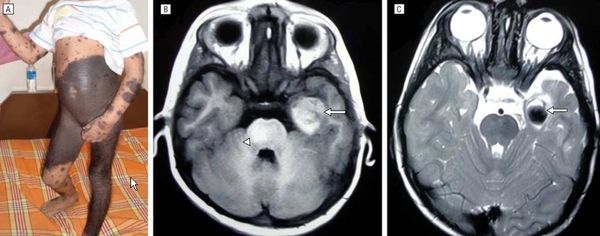

Нейрокожный меланоз

В редких случаях развивается нейрокожный меланоз — заболевание, при котором меланоциты разрастаются в центральной нервной системе. К таким нарушениям может приводить мутация гена BRAF [50] .

Факторы риска развития нейрокожного меланоза:

- гигантский невус на спине (более 40 см);

- множественные невусы-спутники — чем их больше, тем выше риск;

- более двух средних невусов, особенно если помимо них много других невусов.

Болезнь тяжелее переносят дети младше 10 лет.

В исследовании американских учёных меланоз диагностировали у 26 из 379 пациентов с большими врождёнными невусами [12] . Заболевание может протекать без симптомов и случайно выявляться при МРТ, но в некоторых случаях оно сопровождается неврологическими нарушениями:

- головной болью, вялостью и рвотой;

- отёком диска зрительного нерва;

- параличом черепно-мозговых нервов и судорогами;

- увеличением окружности головы;

- нарушением координации;

- задержкой или недержанием мочи и кала.

Неврологические симптомы могут развиться из-за кровоизлияния в желудочки головного мозга, нарушения циркуляции спинномозговой жидкости, сдавления спинного мозга или злокачественного перерождения меланоцитов [3] [14] .

Симптомы появляются примерно в двухлетнем возрасте. Прогноз чаще неблагоприятный, даже если нет злокачественных новообразований [15] . В одном обзоре были изучены 39 случаев симптоматического нейрокожного меланоза: более половины пациентов погибли в течение трёх лет после появления неврологических нарушений [34] .